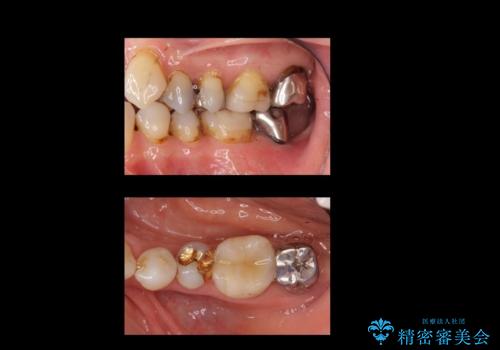

- 半分残していた奥歯の虫歯の状態が良くない為、抜歯をしてインプラントをしました。

向かい合わせの歯の治療も、神経の治療からセラミックのかぶせ物まで行っています。

- 69.4万円 内訳:左下7(ストローマンインプラント24.2万円 インプラント用仮歯2.2万円 骨増成5.5万円 カスタムアバットメント11万円 FGG(遊離歯肉移植術)11万円 静脈内鎮静5.5万円)費用は治療当時の料金となります